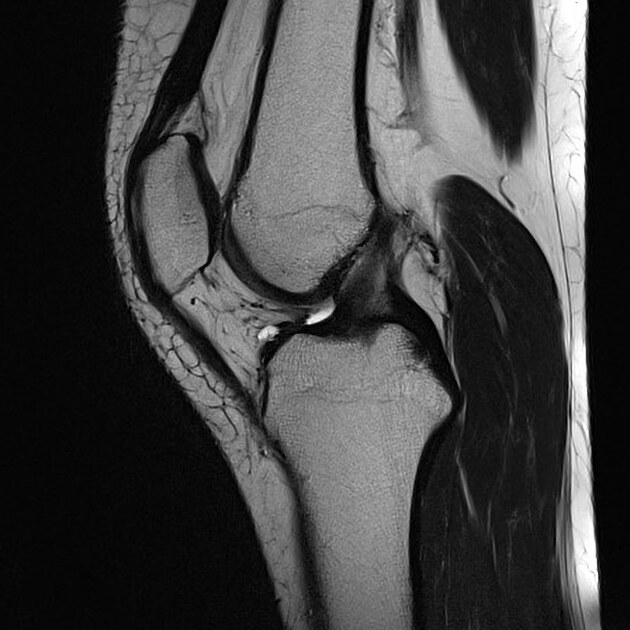

Jumping Knee Mri . May demonstrate a thickened patellar tendon. The prevalence of jumper's knee is high in sports characterized by high demands on leg extensor speed and power, such as volleyball,. Some suggest instead that jumper's knee is a mid. It is well seen on sagittal mri as increased tendon thickness greater than 7 mm or as intrasubstance high signal intensity. Some authors suggest that the ap diameter of a normal tendon, at its proximal. In patients with jumper’s knee, most reliable mri finding is focal proximal tendon thickening with an associated increase in anteroposterior diameter. Jumper’s knee is the common name given to a partial tear of the patellar insertion of the patellar tendon, most commonly seen in younger.

The prevalence of jumper's knee is high in sports characterized by high demands on leg extensor speed and power, such as volleyball,. Jumper’s knee is the common name given to a partial tear of the patellar insertion of the patellar tendon, most commonly seen in younger. Some suggest instead that jumper's knee is a mid. Some authors suggest that the ap diameter of a normal tendon, at its proximal. May demonstrate a thickened patellar tendon. In patients with jumper’s knee, most reliable mri finding is focal proximal tendon thickening with an associated increase in anteroposterior diameter. It is well seen on sagittal mri as increased tendon thickness greater than 7 mm or as intrasubstance high signal intensity.